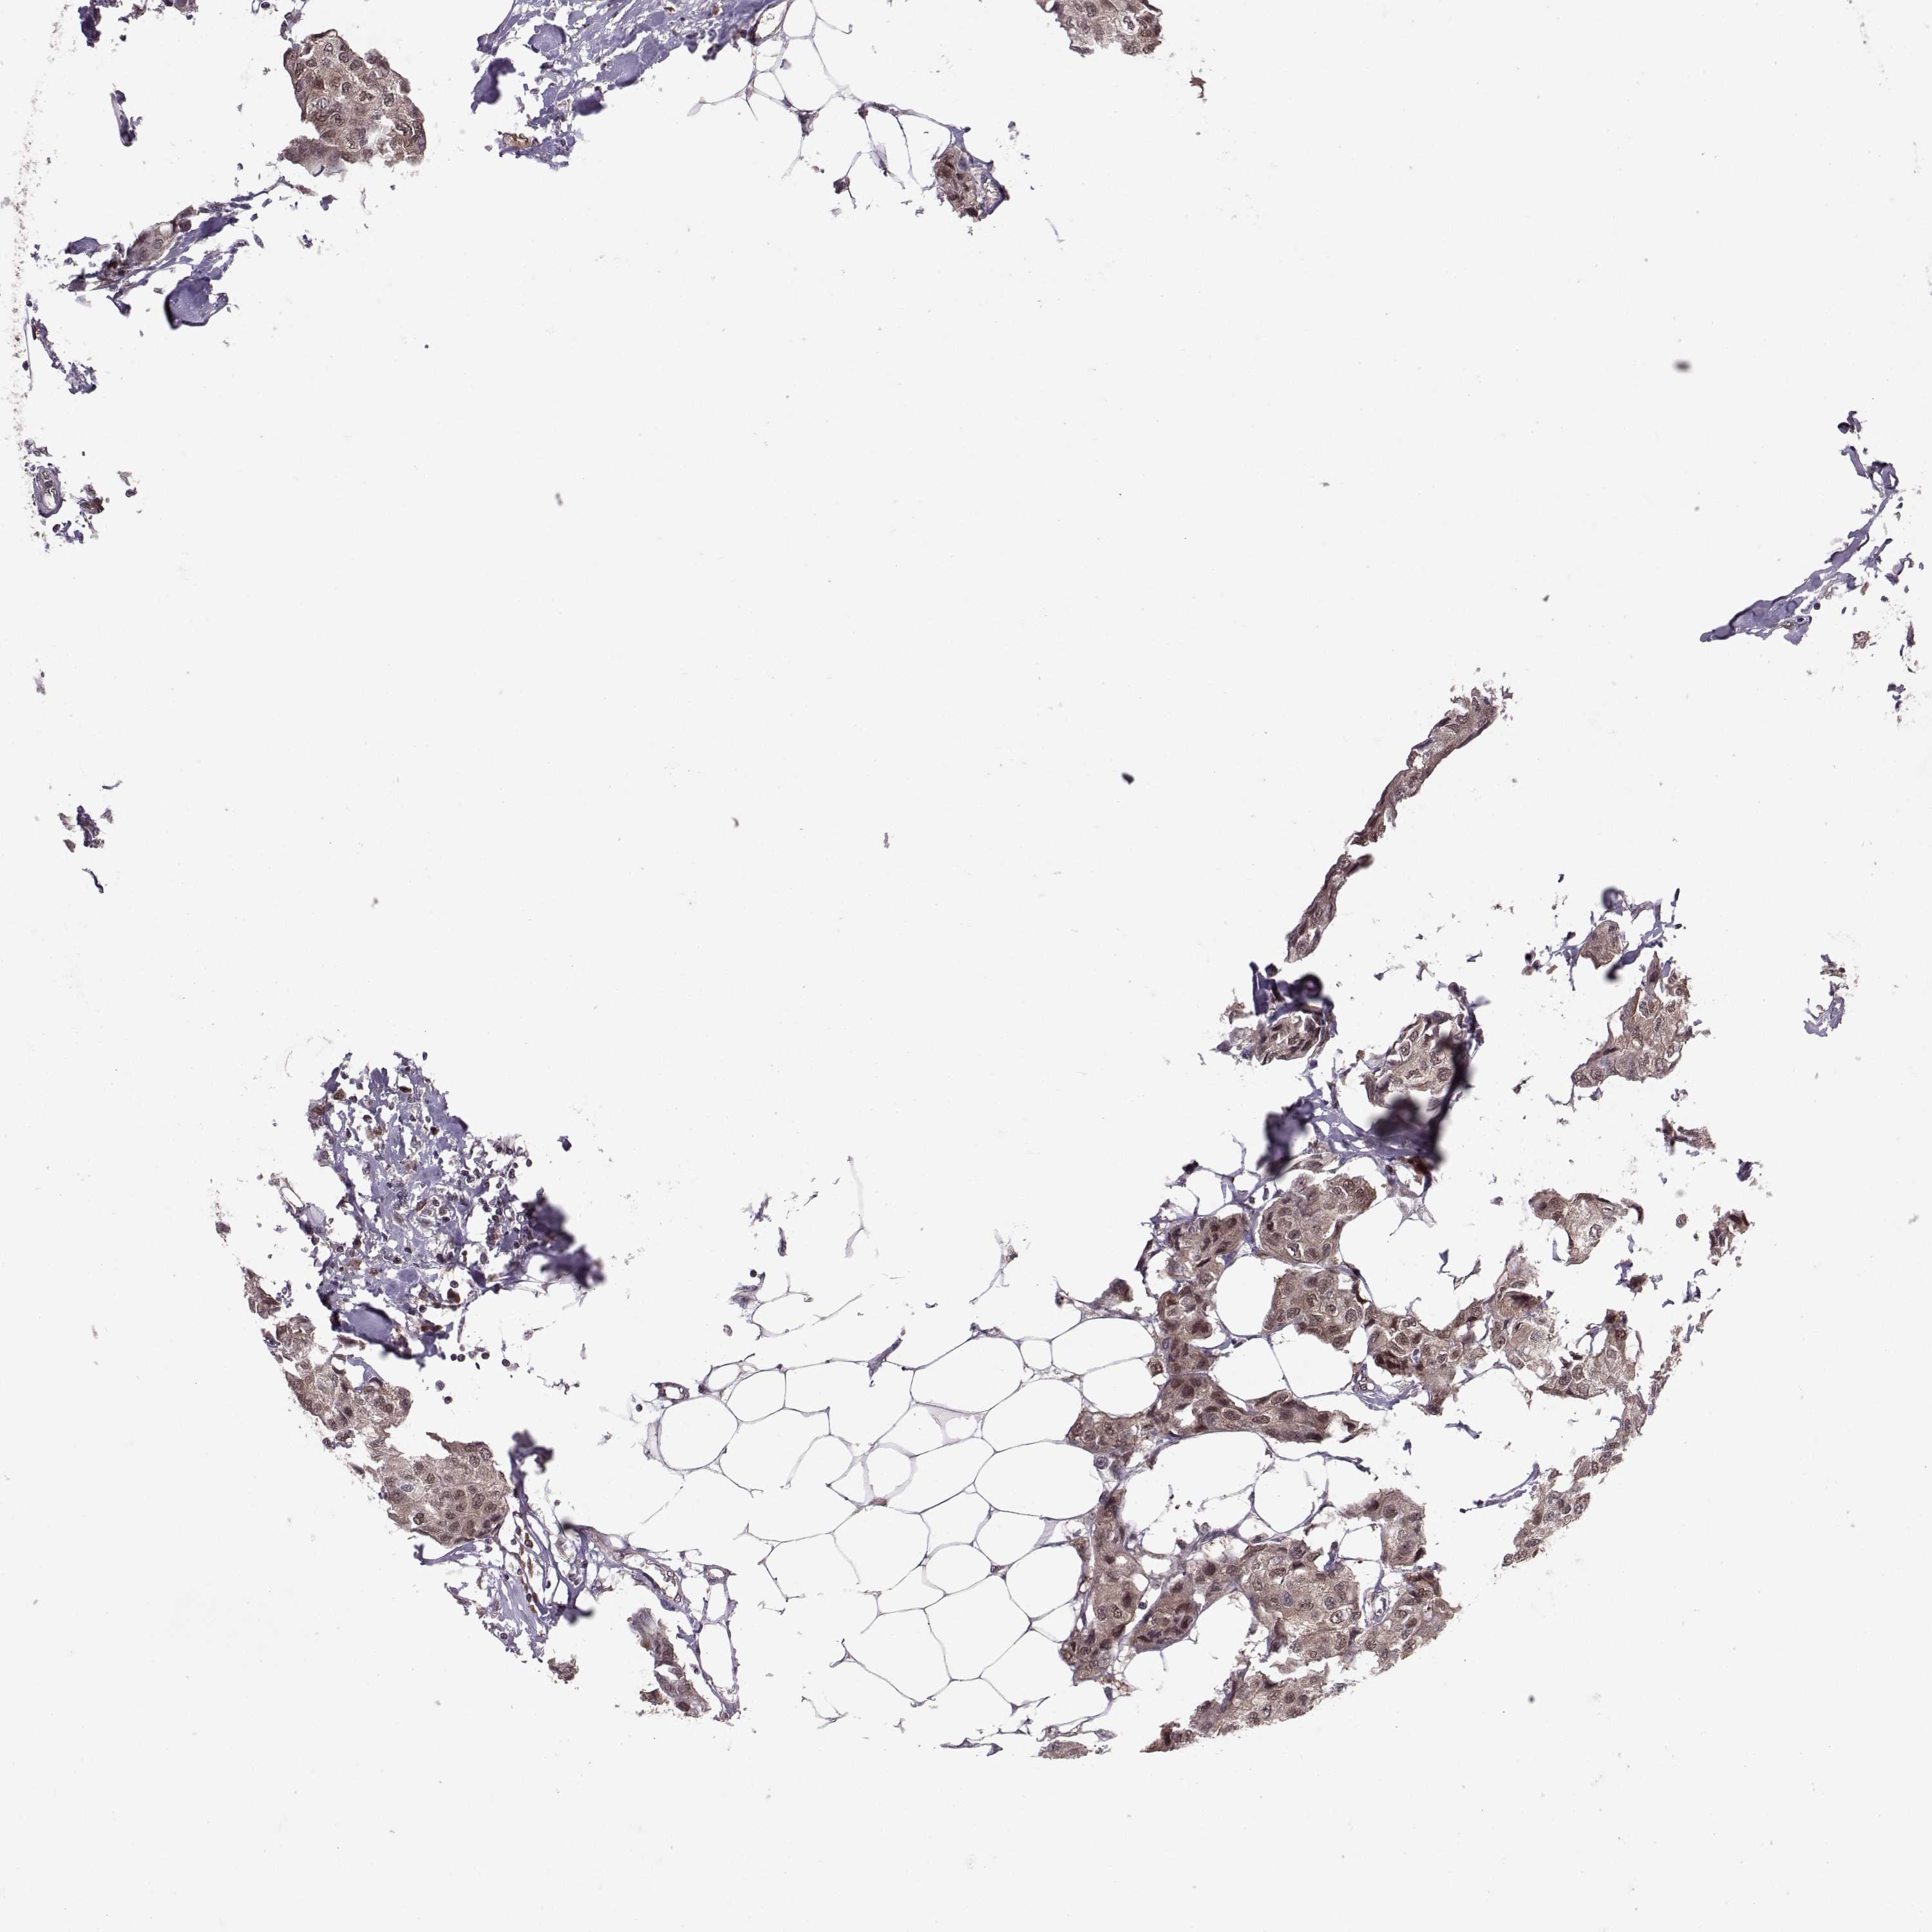

CANCER BREAST CANCER Show tissue menu

BRCA TCGA BRCA VALIDATION PROTEIN EXPRESSION